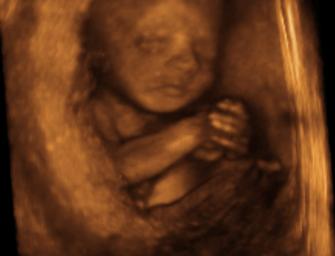

This means that babies aborted in the 2nd and 3rd trimester are “overwhelmingly” aborted because their mothers had difficulty making arrangements to kill them. These women, therefore, are not suffering from serious health problems. Rather, 2nd and 3rd trimester abortions are done “overwhelmingly” on healthy mothers with healthy children. Below you can see the hand of a baby aborted at 28 weeks. Is it acceptable for a woman to have an abortion this late because she was unable to arrange an abortion earlier?